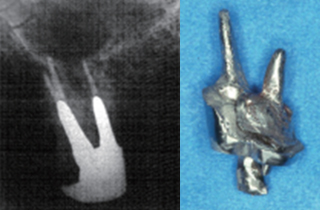

신경치료 후 남아있는 치질이 너무 짧거나 부족한 경우

크라운을 씌우기 전 치아안쪽에 기둥을 세우고 보강해주는 과정이 필요합니다.

포스트의 종류는 두가지가 있는데 사진은 기공소에서 맞춤형으로 제작된 포스트입니다.